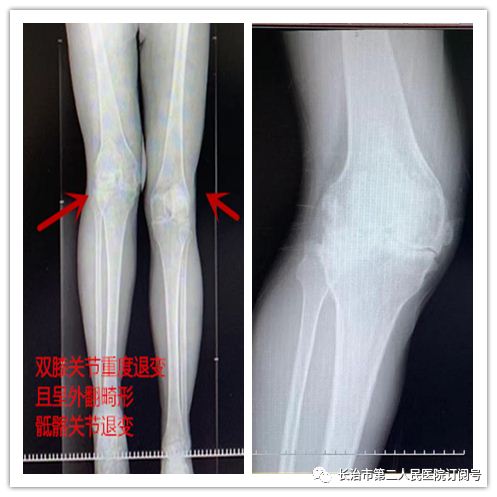

术前X光检查显示:王先生呈跛行步态,双膝双膝关节屈曲、外翻畸形,右膝外翻达20°,双膝关节增生、变形,关节周围压痛阳性,右膝关节活动范围40-50°(右膝活动度基本缺失),左膝关节活动范围30-85°。诊断为双膝重度骨关节炎,强直性脊柱炎。

王先生属于僵直、外翻膝,双膝关节因软组织粘连挛缩使关节腔的显露异常困难,很难达到伸直间隙和屈曲间隙的平衡及假体的最佳放置位置,手术难度极高;由于此类患者行走困难,长期卧床,多伴有重度骨质疏松,加之关节粘连,术中显露困难,容易损伤临近神经,甚至并发骨折,术后膝关节功能恢复欠佳几率大大增加,因此僵直膝关节行关节置换对手术医生的理论知识和临床经验有着更高的要求。

僵直膝、外翻膝均是全膝关节置换手术因术中难度大、术后并发症多、术后满意率低等一直是全膝关节置换手术中对于医生技术水平要求较高的类型。针对此次手术僵直膝+外翻膝更是挑战中的挑战。